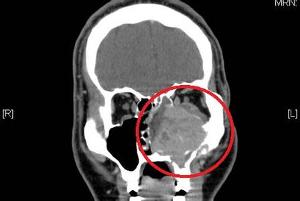

5.X线摄检查眶及视神经孔。有条件时可作眶静造影及CT扫描、磁共振成像(MRl)检查。

诊断据病史,年龄和临床症状。X线可见到钙化点,或视神经孔扩大。B超检查可分为实质性和囊性两种图,前者可能为早期肿,后者代表晚期肿